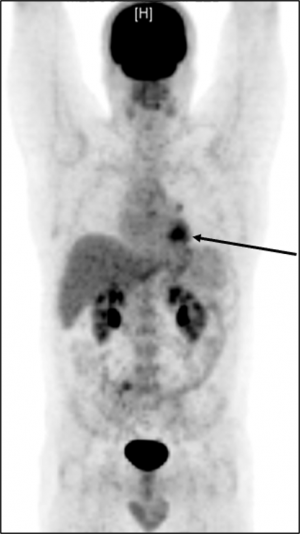

Kanser tedavisine yön veren teknoloji: PET/BT

PET-BT: Pozitron Emisyon Tomografisi (PET) ve  Bilgisayarlı Tomografi (BT) iyi bilinen iki ayrı görüntüleme tekniğinin, (PET – BT) tek bir sistemde toplanmasıyla oluşturulan bir görüntüleme cihazıdır. Anatomik detay için BT, organların yada tümörün metabolizması ile ilgili bilgi için PET kullanılmaktadır.

PET-BT muayenesi özellikle kanser durumunda; hızlı, kapsamlı ve güvenilir bir teşhis sağlar.

Şimdiye kadar, ortak bir bulgu hazırlandı. PET kısmı nükleer tıp uzmanı tarafından, BT kısmı ise radyolog tarafından oluşturulur. Her iki uzman da muayene sonuçlarına birlikte bakmalı ve ardından birlikte bir rapor hazırlamalıdır. Profesör Dr. Dr. Hüdayi Korkusuz sayılı olan  iki uzmanığa sahip doktorlardan birisidir. Her iki uzmanılığıda Almanya’da aldı.

Çift uzmanların PET-BT bulguları yüksek kalite standartlarına sahiptir. Prof. Korkusuz’dan istediğiniz zaman ikinci bir görüş alabilirsiniz. Bunun için bize PET-BT görüntülerinizi göndermeniz yeterlidir.

Burada bir akciğer kanseri görebilirsiniz.